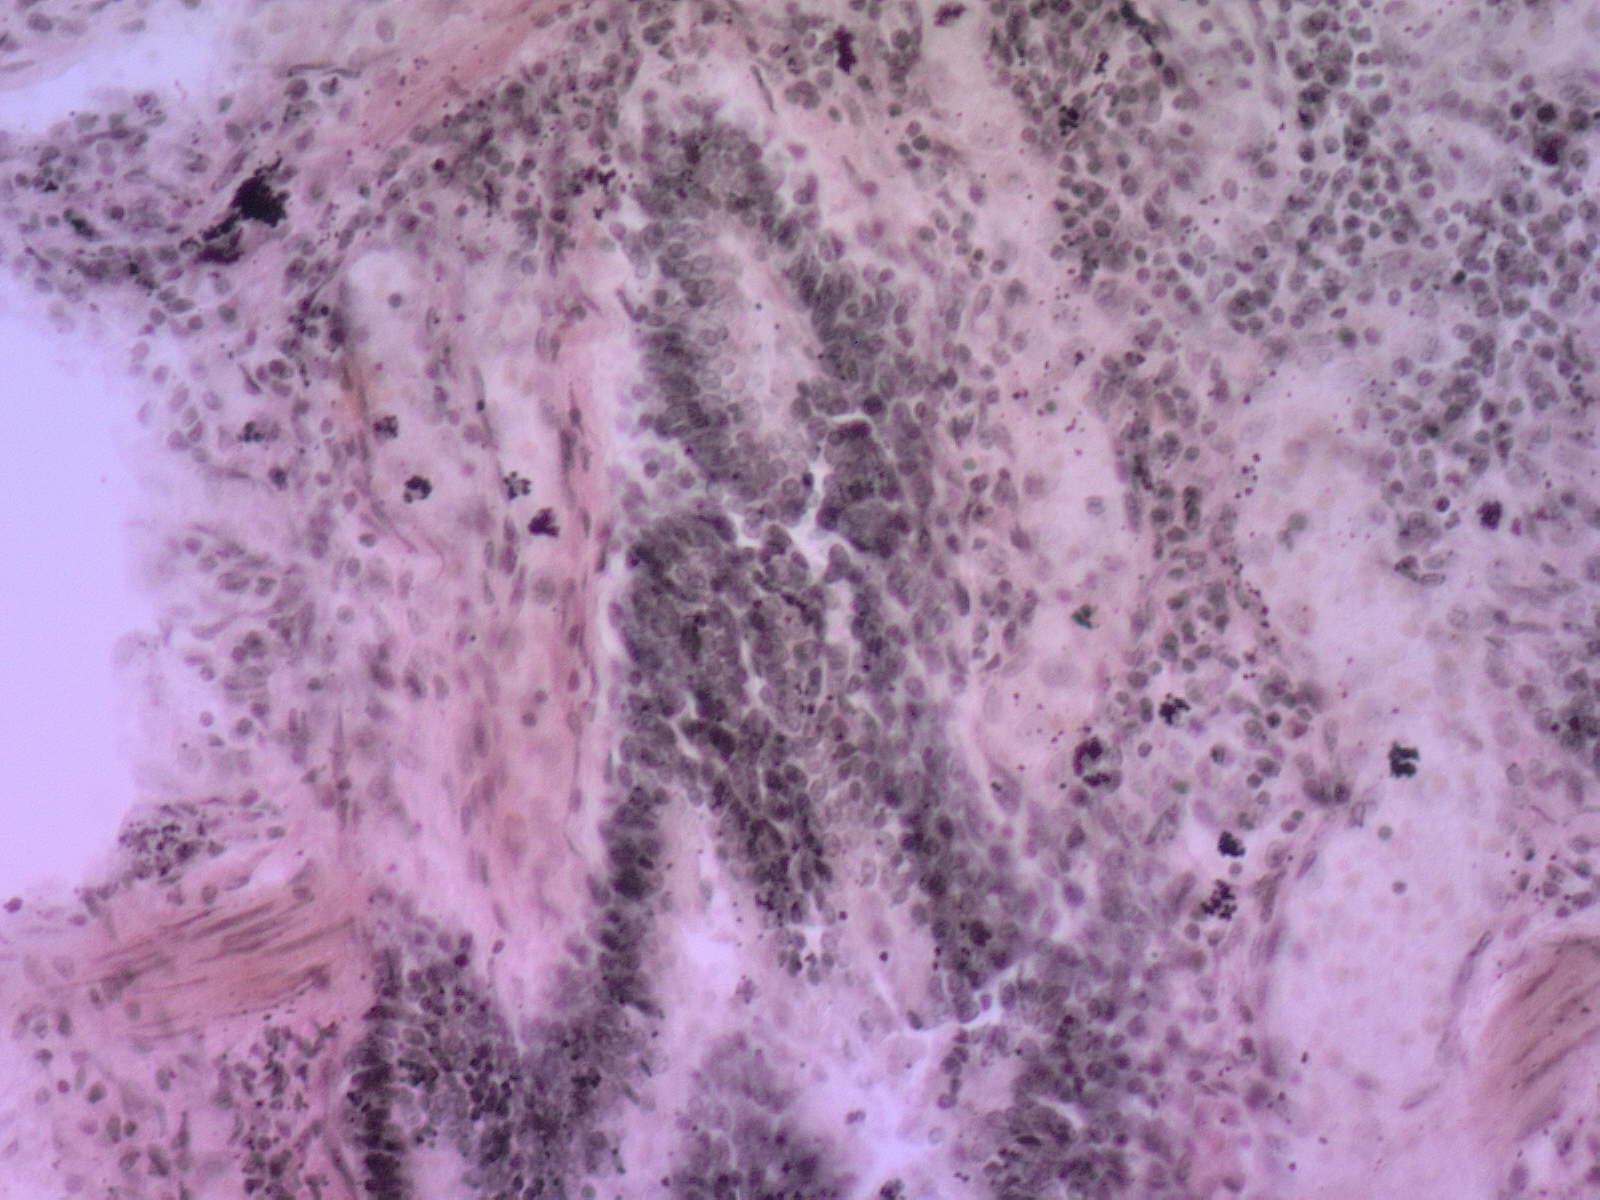

290. Антракоз легкого

Гистологическая структура легкого резко изменена из-за массив­ных тяжей соединительной ткани, эмфизематозных полей, периваскулярного и перибронхиального склероза. Кроме того, имеются оча­говые отложения угольной пыли и круглоклеточные инфильтраты. На большем увеличении угольная пыль определяется в стенках аль­веол; среди волоки истых структур и в цитоплазме макрофагов (пы­левые клетки). Пылевые клетки располагаются и в фиброзных тя­жах, и в просвете альвеол,

Существенные элементы: 1. пылевые клетки

2. угольная пыль

3. поля фиброза

4. периваскулярный склероз

5. перибронхиальный склероз